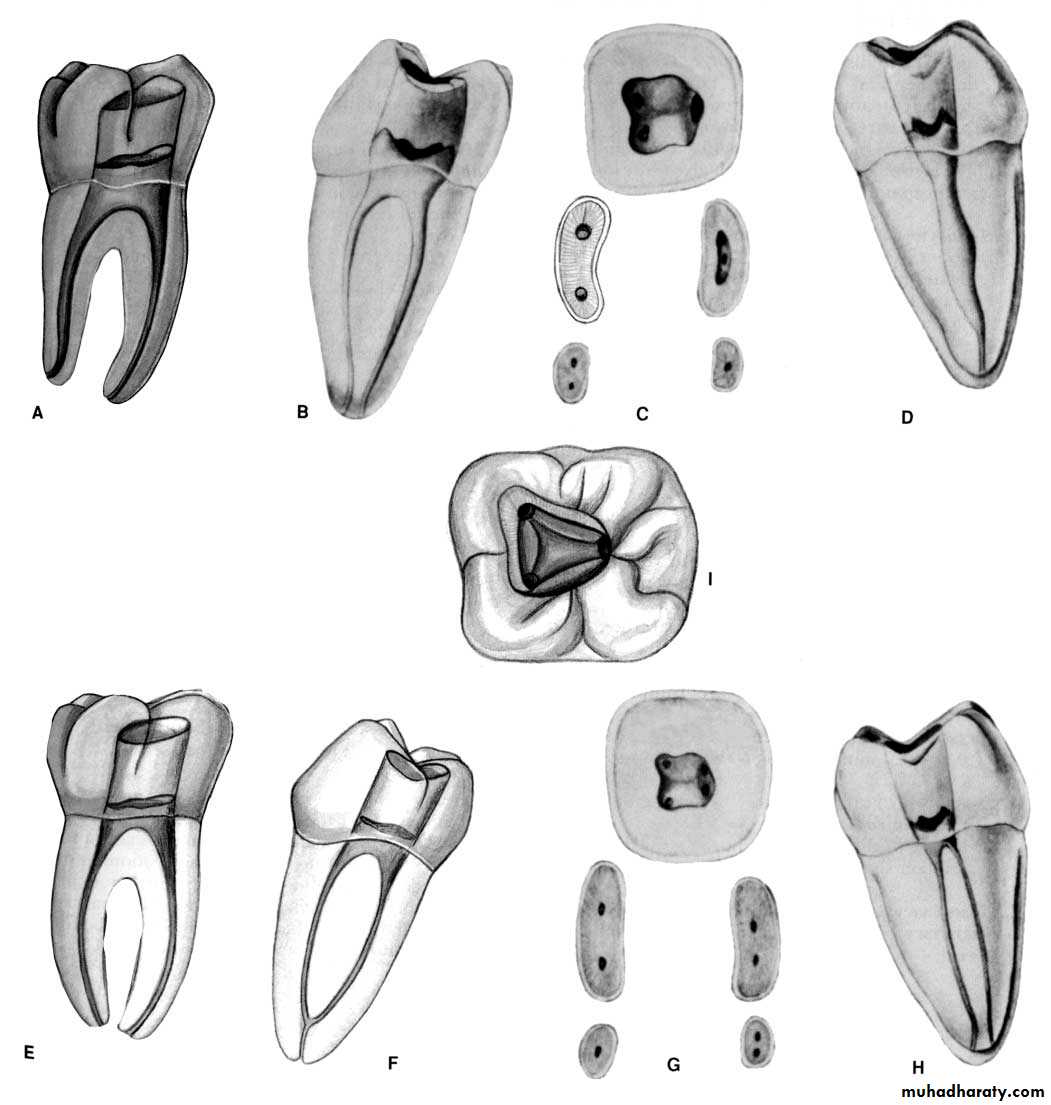

Mandibular first molar.

Distal root can have two canals

Mandibular first molar.* The Man 1st molar usually has two roots, mesial & distal.*Single mesial root with 2 canals.*the distal root is curved mesially.&mesial root curved distally.*the two-rooted molar usually has a canal configuration of three canals.

* The incidence of two distal canals has been reported as 38%.*the pulp chamber is wider mesially than it distally &may have five pulp horns.

*the lingual pulp horns being longer & more pointed.*the floor is rounded &convex toward the occlusal & lies just apical to the cervix.* mesiobuccal canal tend to be much finer than the mesiolingual.*the mesial root in 40-45% has only one apical foramen.

*when a 2nd distal canal is present on the distolingual aspect it tends to curve towards the buccal.*the average length is 21mm.

Mandibular second molar.

* Man 2nd molar presents as a smaller version of the man 1st molar.*the average length is 20mm.*the mesial root has two canal but the distal root usually has one canal.*the mesial canals tend to fuse in the apical third to give rise one main apical foramen.*32-33% of man2nd molars have tendency to fused roots.